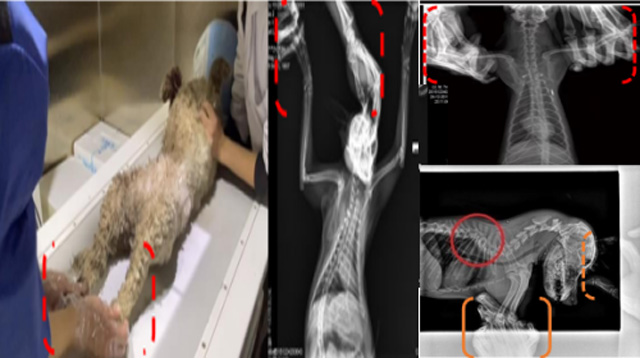

現在寵物醫(yī)療設備得到高速發(fā)展,現在有越來越多的寵物診療機構配置X射線裝置如寵物DR。寵物骨折或者有其他疾病不能通過直觀看出來的。寵物診所醫(yī)生都會使用寵物DR來做輔助檢查。但是有時候寵物醫(yī)生沒有加強防護,就在寵物DR室給寵物拍X片做檢查。這樣也是會受到X射線的輻射。因為X射線上崗是屬于職業(yè)病危害崗位。長期的輻射會對人體造成一定的危害。寵物醫(yī)生也需要接受X射線照射的上崗前都必須進行放射工作人員的職業(yè)健康體檢。體檢不合格的話是不能擔任放射工作的。未經上崗前職業(yè)健康體檢的勞動者從事接觸職業(yè)病危害作業(yè)的行為,已經違反了《中華人民共和國職業(yè)病防治法》第三十五條規(guī)定,依據《中華人民共和國職業(yè)病防治法》第七十五條規(guī)定,需要進行整改罰款。開展寵物放射診療活動,在日常工作中,對本機構的X射線危害的職業(yè)病防治,需要知道并做到以下內容: